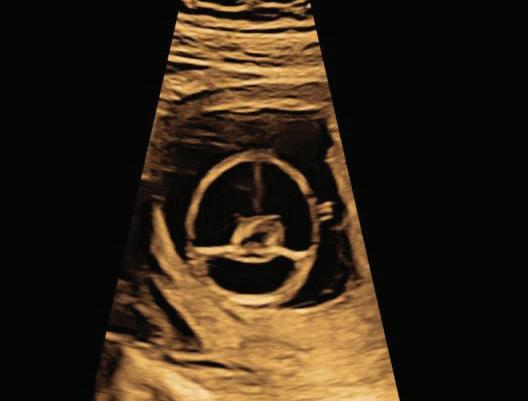

2. NUCHAL TRANSLUCENCY (NT) SCAN

• Done @11–13+6 weeks.

• CRL 45–84 mm.

• This is the cornerstone of first trimester screening.

1. NT is the sonographic appearance of subcutaneous accumulation of fluid behind the fetal neck, below the skin in the first trimester of pregnancy.

2. Measured in mid-saggital section only.

3. Measured between 11-14 weeks.

4. CRL between 45-84mm.

5. Magnified to include only head and upper thorax.

6. Fetus should be in neutral position.

7. Demostrate fetus separate from amnion.

8. Measurement should be ON to ON (cross bar of the callipers should be such that it’s hardly visible and merges with white line, not nuchal fluid).

During the scan more than one measurement should be taken and maximum value should be considered.